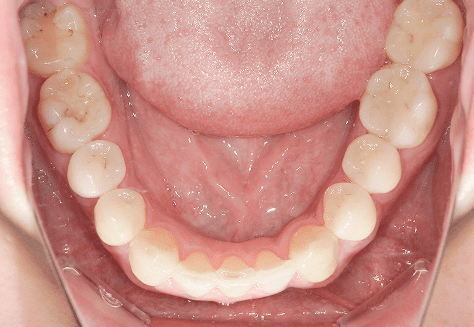

S.K

治療前

治療後

主訴

歯が重なっていて気になる。前歯が出ていて唇が閉じにくい。ハミガキがしにくい。

診断

上顎前突・叢生

年齢/性別

20代/男性

抜歯部位

上下第三大臼歯

使用装置

上下インビザライン

保定装置

上下ビベラリテーナー

料金

初回資料採得・・・・・・・30,000円

診断料・・・・・・・・・・33,000円

動的治療終了時資料採得・・5,500円 -

基本料金

990,000円

診察料金

1,100円×33回

治療期間

3年5カ月